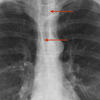

Anterior junction line

Date: 01/11/2010

Views: 5205